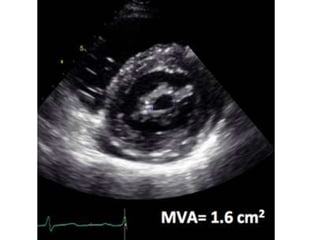

1. MVA Planimetry (Level 1 Recommendation).

planimetry is considered as the reference

measurement of MVA

• Careful scanning from the apex to the base of

the LV PSAX view at the level of mitral valveis

required to ensure that the CSA is measured

at the leaflet tips

• Gain setting should be just sufficient to

visualize the whole contour of the mitral

orifice. Excessive gain setting may cause

underestimation of valve area, in particular

when leaflet tips are dense or calcified.

• Image magnification, using the zoom mode, is

useful to better delineate the contour of the

mitral orifice.

Measuring valve area 1.MVA Planimetry (Level 1 Recommendation). planimetry is considered as the reference measurement of MVA • Careful scanning from the apex to the base of the LV PSAX view at the level of mitral valveis required to ensure that the CSA is measured at the leaflet tips

• 23.

• Gain settingshould be just sufficient to visualize the whole contour of the mitral orifice. Excessive gain setting may cause underestimation of valve area, in particular when leaflet tips are dense or calcified. • Image magnification, using the zoom mode, is useful to better delineate the contour of the mitral orifice.

• 24.

• The optimaltiming of the cardiac cycle to measure planimetry is mid-diastole. This is best performed using the cineloop mode on a frozen image. • Recent reports suggested that real-time 3D echo and 3D-guided biplane imaging is useful in optimizing the positioning of the measurement plane and, therefore, improving reproducibility

• 25.

• In theparticular case of degenerative MS, planimetry is difficult and mostly not reliable because of the orifice geometry and calcification present